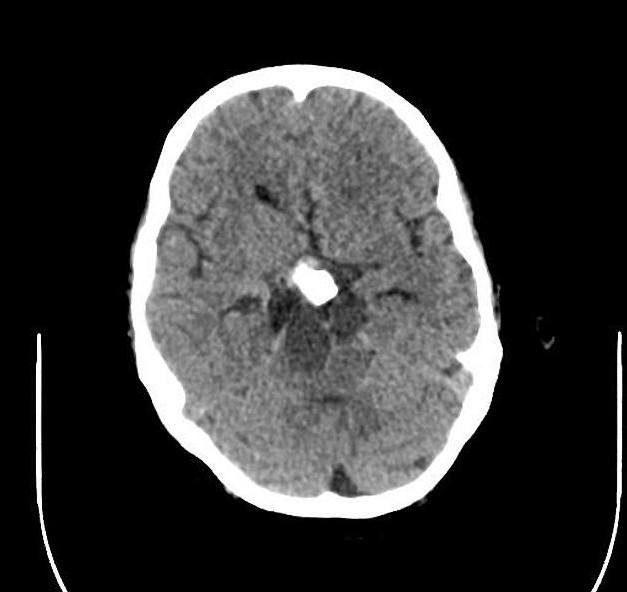

U sọ hầu

» Thông tin: Nam giới – 30 tuổi.

» Lâm sàng: Đau đầu.